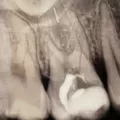

Нужен снимок с инструментом, чтобы было видно на каком уровне он в корне. Но, если несколько врачей сказали, что достать нереально, вероятно так и есть.

• На данном рентгеновском снимке в апикальной трети корневого канала есть отломок инструмента, достать его и качественно обработать канал зуба очень трудно и есть риски возникновения осложнений в будущем в виде периодонтита. Поэтому подобный зуб лечится без гарантии. Возможно, зуб лучше удалить и поставить имплантат.